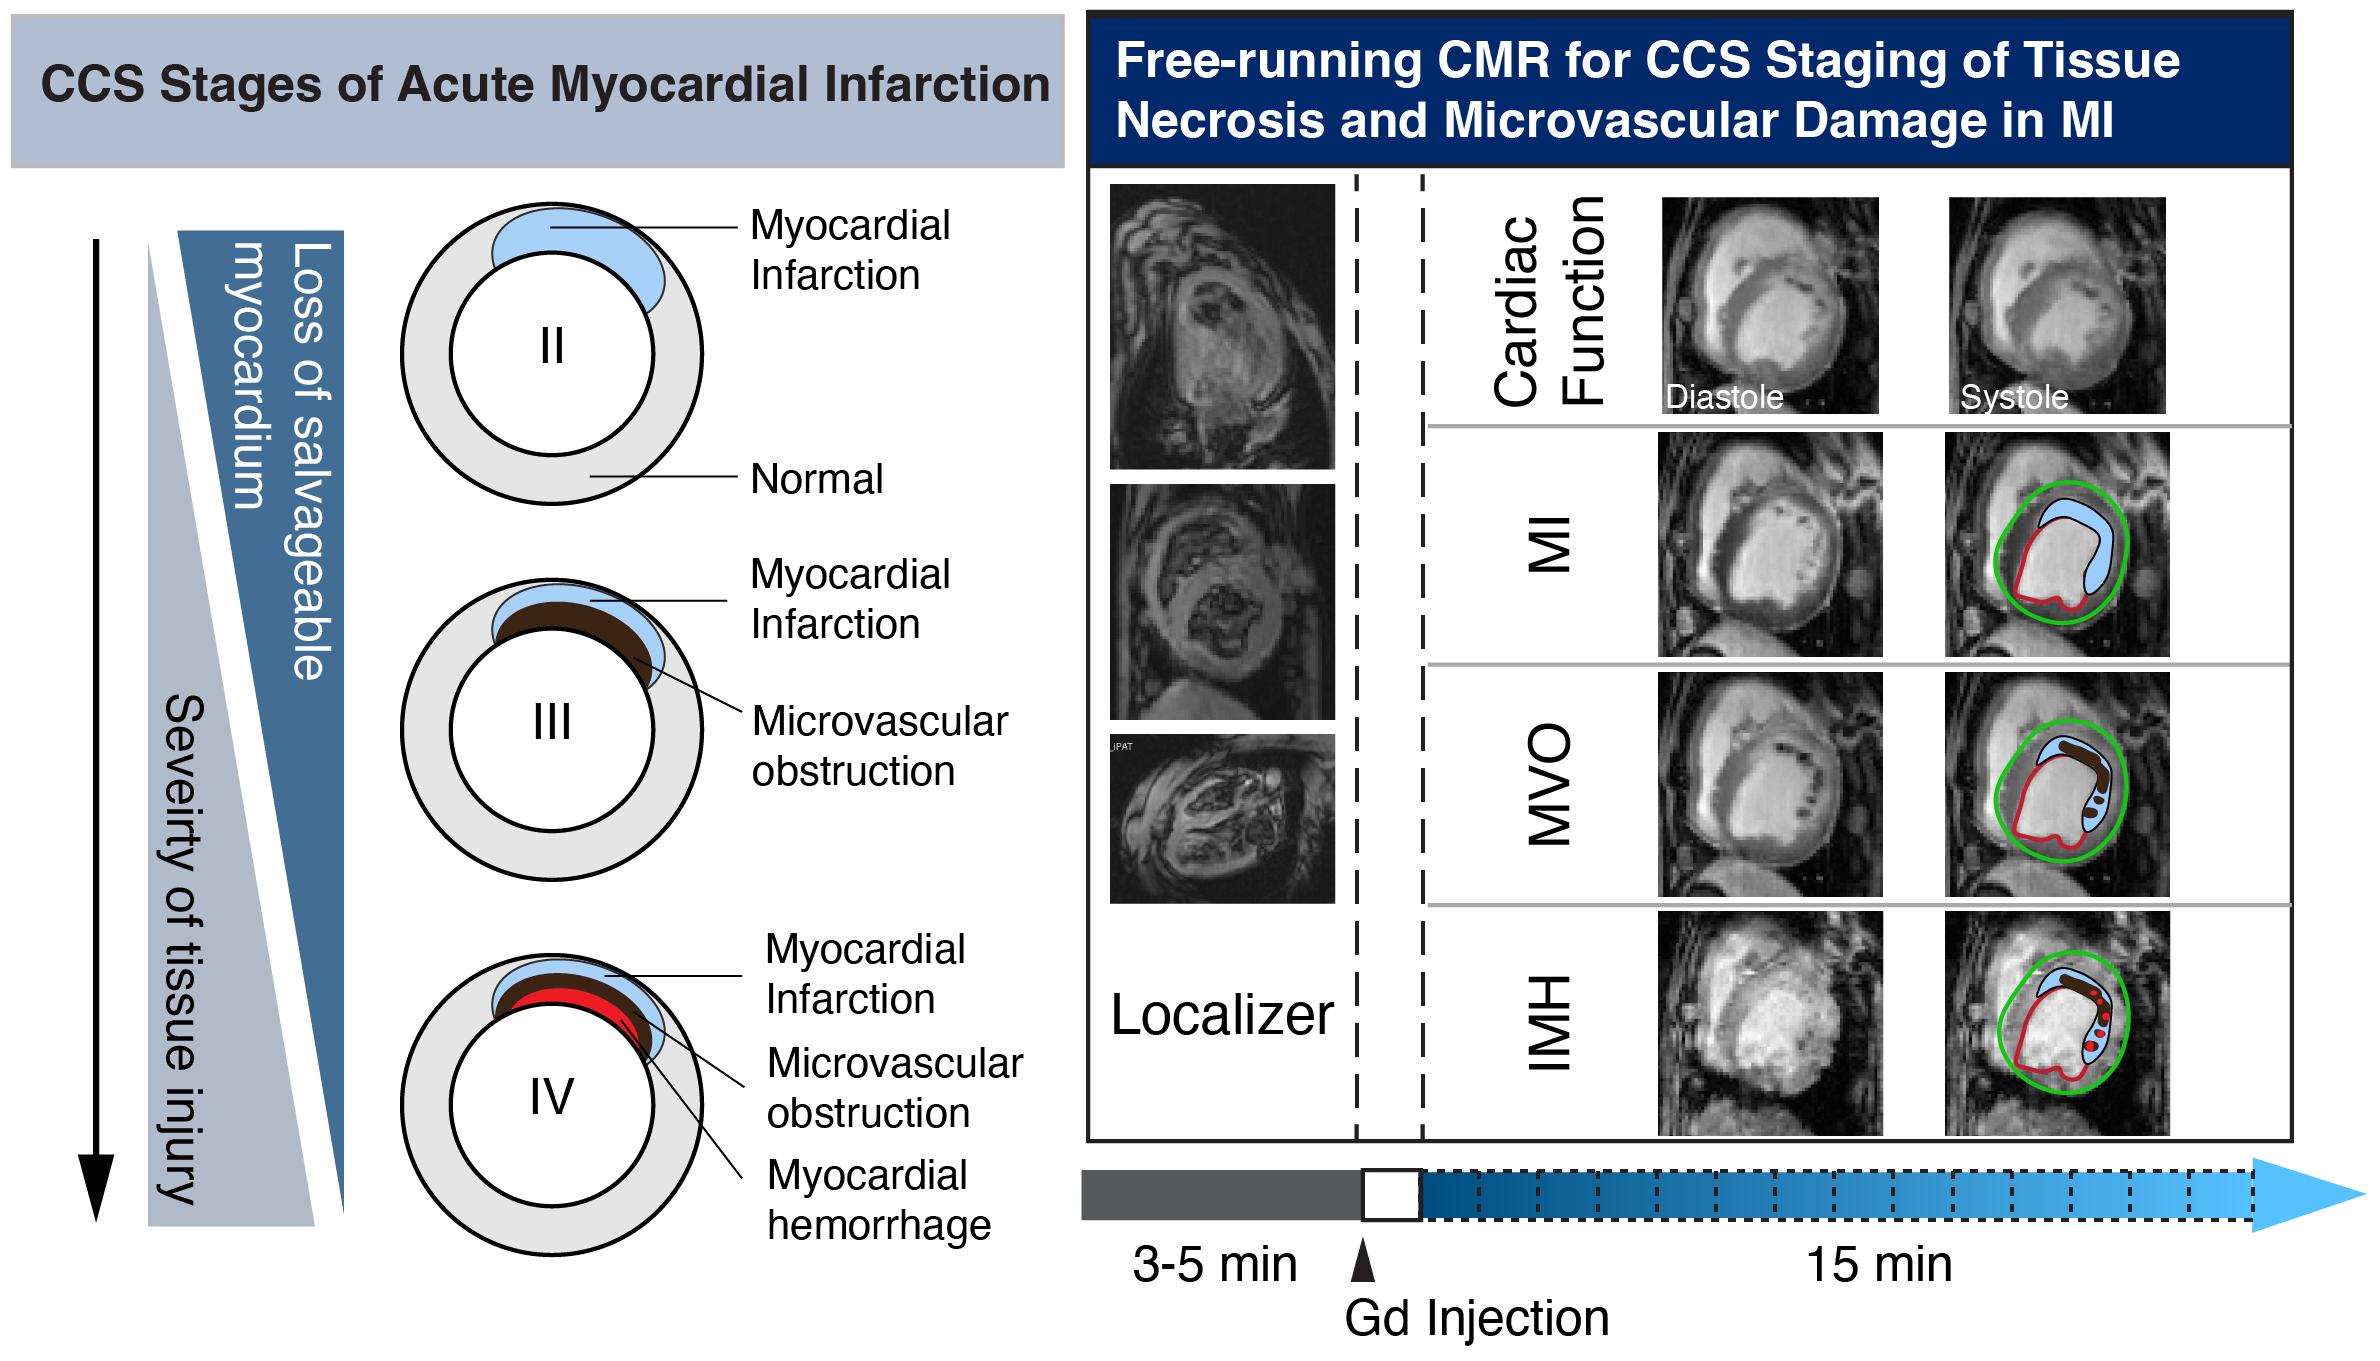

Methods: Image Model: A free-running 3D MRI method with low-rank tensor (LRT) reconstruction2,3 was developed to simultaneously capture cardiac and respiratory motion plus T1 and T2* dynamics after contrast injection for 14 min. Image Reconstruction: Time-resolved data were assigned to 15 bins (~57 sec/bin) and and temporal coefficients were estimated from training data using Bloch-constrained LRT completion. Data acquisition: Canine models with reperfused myocardial infarction (MI) were imaged at weeks 1 (n=12) and 8 (n=9) post-MI in a 3T clinical system with the proposed LRT acquisition and compared to clinical 2D breath-hold sequences. Data Analysis: Left-ventricular ejection fraction (LVEF), MI size and transmurality, microvascular obstruction (MVO) on early/late enhancement (2 and 15 min post-Gd), and intramyocardial hemorrhage (IMH) volume (T2*w, TE=11.42 ms) were measured using proposed and conventional methods. Histological Validation: Trichrome and Prussian Blue staining were used to validate MI and IMH.

Conclusion: Proposed cardiac MRI approach permits determination of tissue injury within 20 min in scan time without breath-holding or ECG gating, enabling CCS staging (Stages II–IV) with strong agreement to conventional protocols. While the method remains to be tested in patients, it has the capacity to facilitate efficient use of cardiac MRI for staging severity of tissue injury in MI.

Figure 1. Schematic diagram of Canadian Cardiovascular Society (CCS) staging of irreversible myocardial infarction (Stage II – Stage IV) and proposed free-running CMR protocol within 20 min to determining cardiac function, severity of tissue necrosis and microvascular damage in reperfused MI with whole-heart coverage.